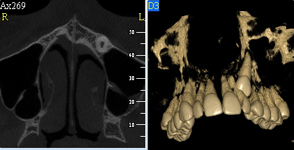

NewTom GiANO

Jedná se o nejnovějším přístroj ze skupiny dentálních hybridních CBCT (3D) + 2D (pan i ceph) systémů. Přístroj umožňuje na základě jediného snímkování vytvořit všechny typy RTG zobrazení, které jsou pro lékaře potřebné.

Používaná technologii tzv. „kuželového paprsku“ a speciální senzory pro minimální zátěž při snímkování pacienta

(o více jak 80% nižší dávka proti klasickému CT).

Pomocí tohoto přístroje je možné zjisti skutečnou situaci v čelistních kostech pacienta tedy množství kosti - můžeme změřit skutečnou šířku i výšku kosti, i kvalitu kosti (hustotu) v místě uvažované implantace. 3D (tříprostorové) zobrazení umožňuje

zvýšit prostorovou představu operatéra ještě před vlastní operací a zároveň pacientovi lépe objasnit a ukázat oblast plánovaného zavedení implantátu.

Pacient „neumí číst“ RTG snímky, ale díky 3D zobrazení vidí „svoji skutečnou čelist“ – např. jak je nízká či úzká, vidí průběh nervu nebo velikost čelistní dutiny, což mu umožní i pochopení nutnosti v některých případech provést pomocné zákroky

ještě před vlastním zavedením implantátu (více - Augmentace - kostní štěp, sinus lift, kostní granulát...).